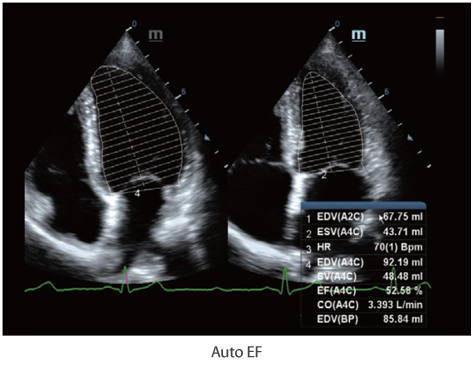

Многофункциональная система DC-60 Exp с X-Insight представляет собой комплексное решение, которое помогает управлять повседневной клинической практикой с легкостью и уверенностью.

Основываясь на глубоком понимании потребностей клиентов, компания Mindray разработала систему DC-60 Exp с X-Insight, чтобы обеспечить высокую производительность и точность визуализации вкупе с наглядностью, исключительной интеллектуальностью и огромным опытом.